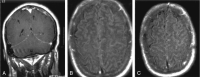

F<sc>ig</sc> 6.

Fig 6.

Patient 2 with meningeal involvement. A, Coronal gadolinium-enhanced T1WI shows abnormal enhancement of the tentorial meninges and focal increased meningeal enhancement in the left parietal lobe. Arrows indicate subtle enhancement in the sulci. B and C, FLAIR images show increased signal intensity in the sulci, more prominent on the left than on the right.